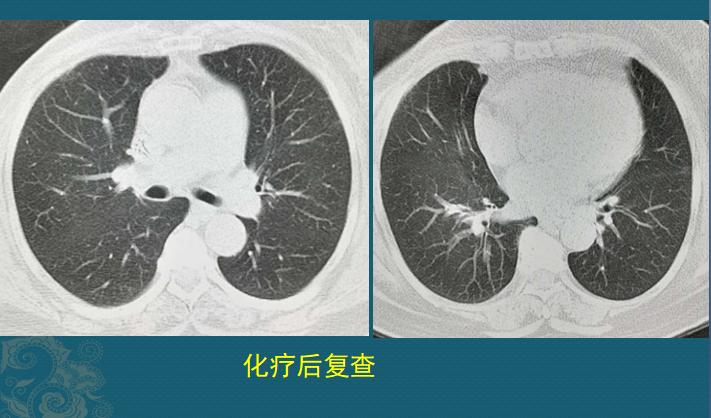

做了两个周期的化疗,吉西他滨+长春瑞滨,今天复查CT,转移瘤和胸腔积液都看不到了:

就像施了一道魔法,癌细胞和胸腔积液都消失了。以至于我们仔细对比乳腺、肋骨和血管壁钙化特征,确实是同一个人,CT片子没有搞错。